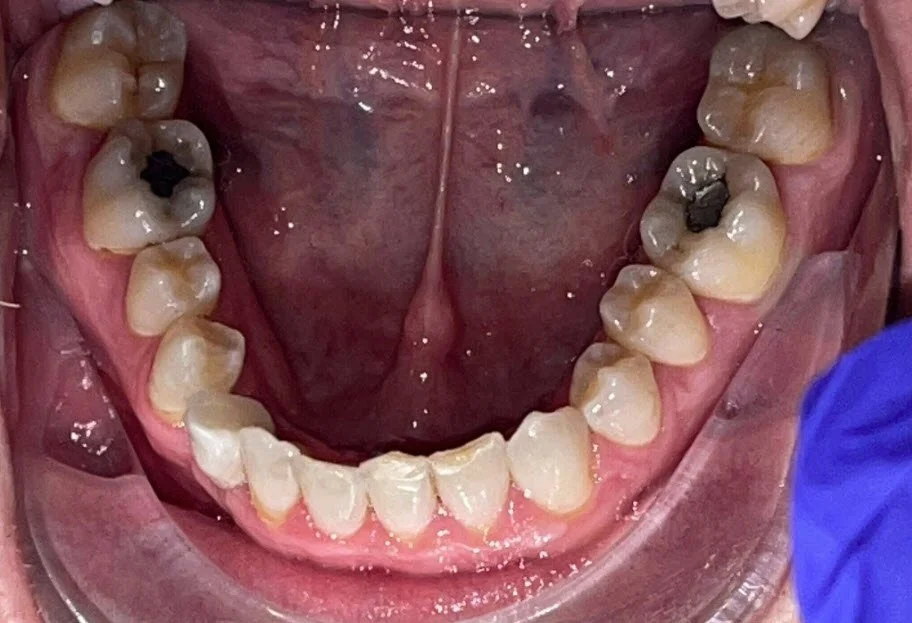

Implant

Before